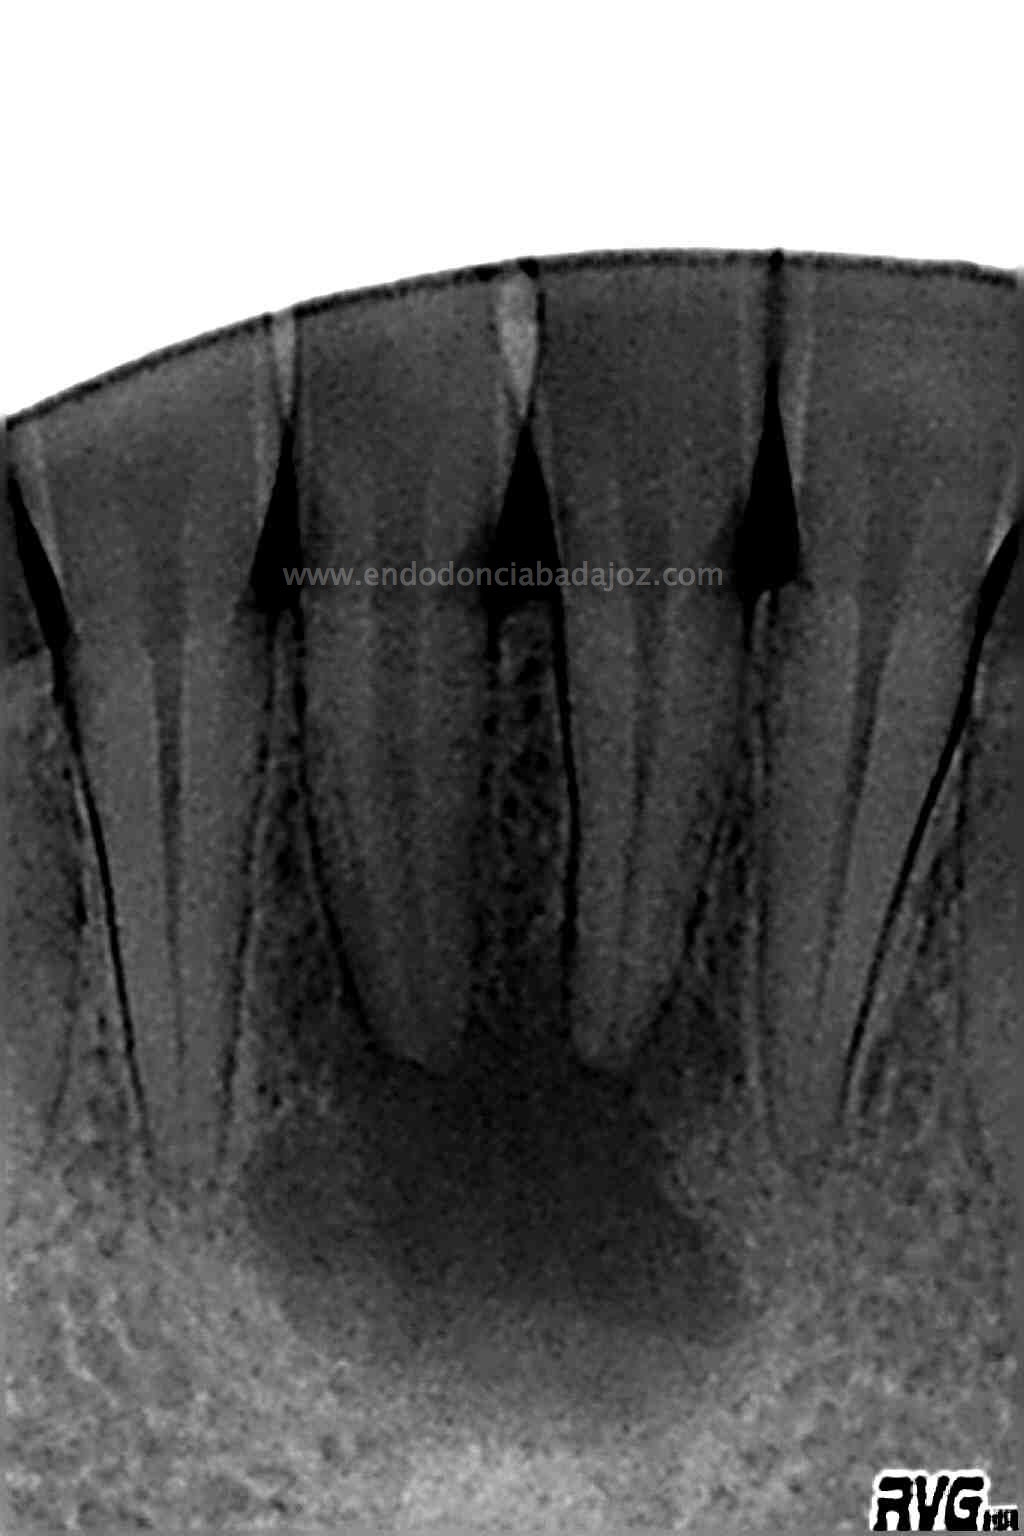

Se le volvió a llamar para otra revisión al año y medio para ver como iba evolucionando:

(revisión al año y 6 meses)